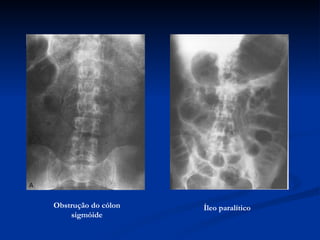

Obstrução do cólon sigmóide Íleo paralítico

Obstrução do cólonsigmóide Íleo paralítico